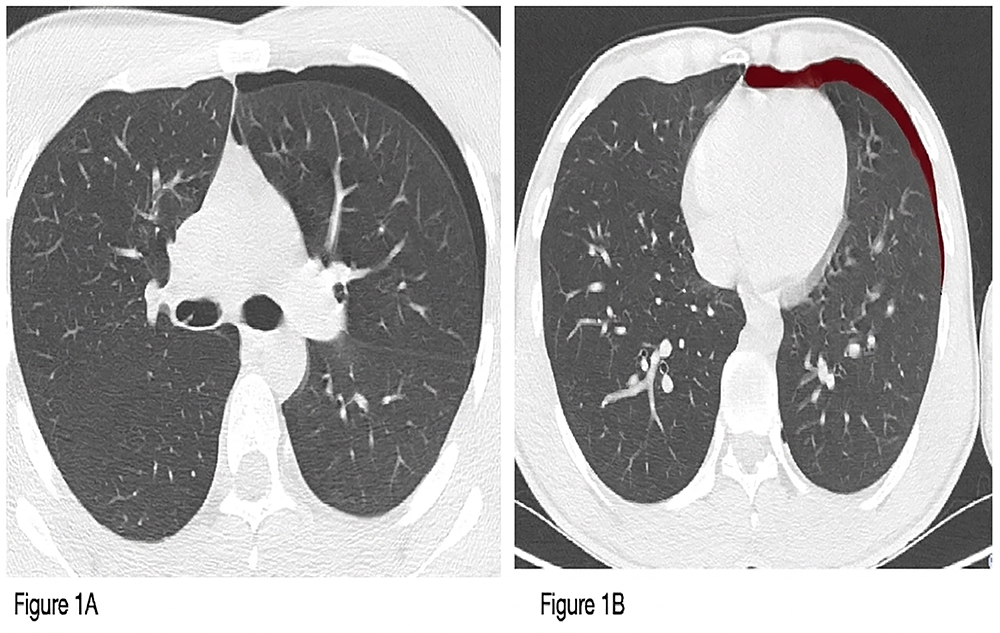

Air densities representing pneumothorax were stained with the tumor tracking method, and volume measurements were calculated (Figure 1).

Figure 1. Pneumothorax volume measurement with the tumor tracking method. (A)Pneumothorax image on thorax tomography. (B) Measurement with the tumor tracking method